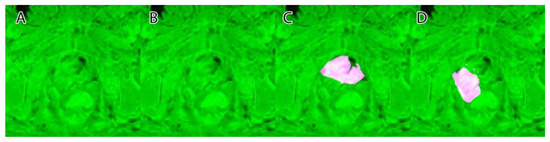

Their overlapping segmentation of PI-RADS 3, PI-RADS 4, and PI-RADS 5 lesions were considered as ground truth, as seen in Figure 4.

A sample of the ground truth marking can be seen in Figure 4.

Figure 4. Ground truth: (A)—PI-RADS 3; (B)—PI-RADS 4; (C)—PI-RADS 5; (D)—extraprostatic invasion.